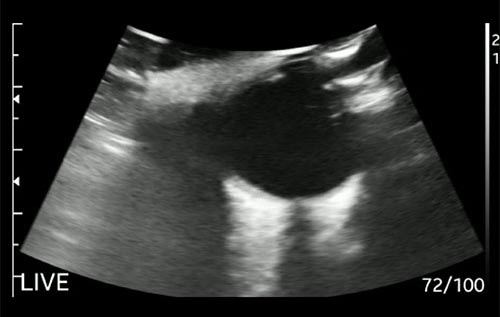

Semana 6

Paciente 58 anos, hipertenso, hepatopata, evoluindo com dispneia e aumento do volume abdominal. Quais achados podemos ver na imagem?